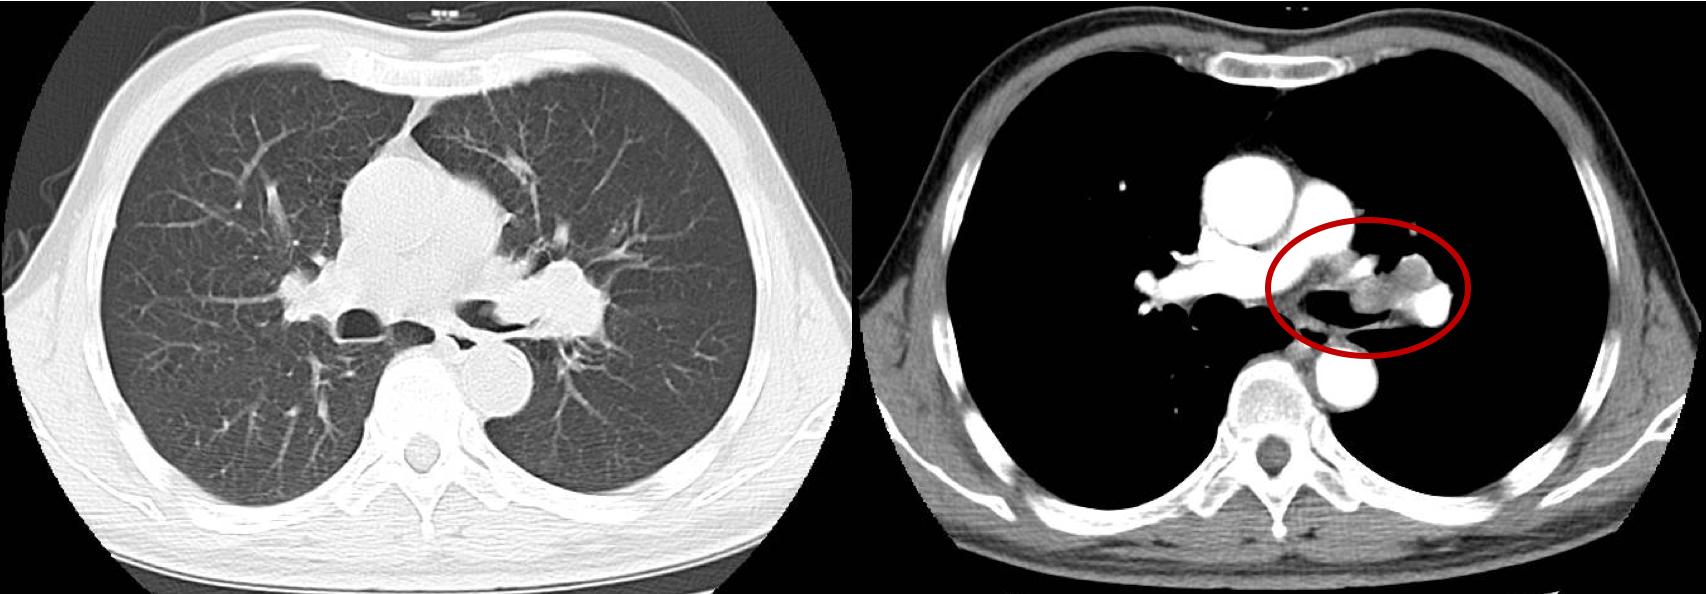

我们选了一个副作用比较小的方案:白蛋白紫杉醇+卡铂,考虑到病人身体情况,我们给减量了20%。2个周期化疗之后,肿瘤明显缩小了,支气管再次通畅,老刘的呼吸困难明显改善。

接下来面临一个关键的选择,做不做手术?如果没切干净,白挨一刀,术后还是得做放疗。而且左全肺切除之后,病人的生活质量肯定会下降一大截。

我们给病人做了分侧肺功能检测(肺灌注显像),结果发现,老刘的左肺功能只占到全肺的20%,也就是说,左侧的肺功能本身也不是很多了。

肺灌注显像

老刘思虑再三,接受了手术。

我们给他做了左全肺切除,最终病理报告显示:瘤床经全部取材,未见明确癌残留!

肿瘤达到了病理完全缓解

非常幸运,化疗杀死了全部的癌细胞!这在医学上叫作“病理完全缓解”,是一个非常小概率的事件,被老刘赶上了!